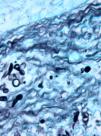

Case descriptionA 60-year-old man presented with a crusted, purple plaque on the left hand (Fig. 1). The lesion was painless and the patient could recall no history of injury at that site. He had undergone bilateral lung transplantation 4 months previously and was receiving immunosuppressive therapy (500mg mycophenolate mofetil, 1mg tacrolimus, and 15mg prednisone daily). A skin biopsy was taken for histopathological examination and microbiological culture. Histopathology revealed suppurative, granulomatous inflammation in the dermis and hypodermis. The lesion was composed of lymphocytes, epithelioid macrophages, multinucleated giant cells, and aggregates of neutrophils in the center of the granulomas (Fig. 2). Periodic acid-Schiff (PAS) stain revealed round-shaped, occasionally septate, fungal structures within the cytoplasm of some giant cells that were associated with extracellular fungal hyphae (Fig. 3).